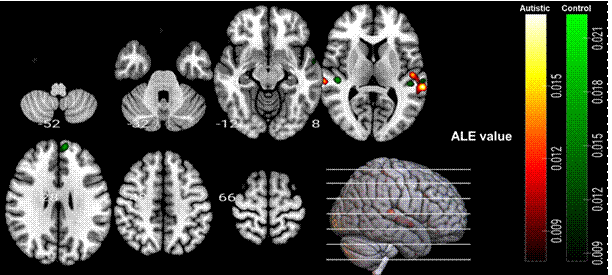

组内分析表明,在听觉语言理解任务中,两组被试的双侧颞上回(bilateral STG)都被激活,非孤独症组被试的左侧额上回(left SFG)和背内侧前额叶皮层(dmPFC)被激活(见图2)。此外,组间分析表明,与非孤独症对照组相比,孤独症组的右侧颞上回(right STG)、左侧颞中回(left MTG)和脑岛(insula)显示较低的激活,而孤独症组在任何区域相对于非孤独症组均未显示激活增加(见图3)。

图2. 组内分析ALE结果(孤独症组和非孤独症组的任务vs.基线)